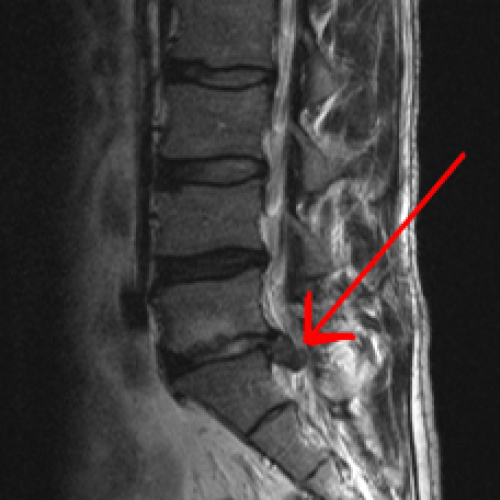

Αποτελεί μια από τις συχνότερες αιτίες χαμηλής οσφυαλγίας με συνοδό ισχιαλγία και ριζιτική συνδρομή (άλγος και μούδιασμα κάτω άκρου).

Από το ιστορικό του ασθενούς η εμφάνιση της οσφυαλγίας μπορεί να είναι είτε με οξύ άλγος κατά την άρση βάρους ή οσφυαλγία λόγω καταπόνησης της σπονδυλικής στήλης κατά την καθημερινότητα (καθιστική εργασία).

Η διάγνωση γίνεται μέσω της κλινικής εξέτασης με τις διάφορες κλινικές δοκιμασίες που υποβάλλει ο ορθοπεδικός τον ασθενή ενώ η επιβεβαίωση καθώς και η σοβαρότητα - μέγεθος της κήλης γίνεται με τη διενέργεια μαγνητικής τομογραφίας της σπονδυλικής στήλης.

Η θεραπεία στα αρχικά στάδια είναι φαρμακευτική αγωγή, φυσικοθεραπείες για μυϊκή ενδυνάμωση των κοιλιακών και ραχιαίων μυϊκών ομάδων, η χρήση ειδικών κηδεμόνων οσφύος καθώς και η έναρξη καθημερινής γυμναστικής - αλλαγή τρόπου ζωής.

Σε εμμένουσα ριζιτική συνδρομή η θεραπεία είναι χειρουργική με μικροδισκεκτομή η οποία προσφέρει άμεση ανακούφιση των συμπτωμάτων.